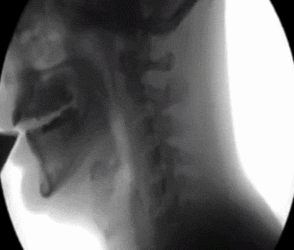

人的喉咙由11块软骨作支架组成,其中最主要、体积最大的一块为甲状软骨,也就是我们所说的「喉结」。

但喉结并不是毫无用处,它可以保护喉壁和喉部前部,以及声带免受伤害。甲状软骨包裹在甲状腺上方的气管前部,与环状软骨相连,可以改变声音。

喉结所在的位置后面有我们的气管、食管,如果用力过猛,可能会产生窒息、呕吐的感觉;另外,还有最重要的颈动脉(维持着头部血供的重要血管),上面有一个特殊的部分叫做颈动脉窦,如果一不小心刺激到它,那结局可就惨了。

颈动脉窦是位于颈动脉上的压力感受器,它能感知血管内血压的变化,一旦它感受到压力过高,就会给心脏和血管发布指令,使心脏跳动速率降低、血管舒张以降低血压,防止过高的血压对大脑造成损伤。

颈动脉窦一般在喉结的两侧,差不多高的水平面,但是在颈部的侧面,一般摸喉结也摸不到那边去,只是有时候摸着摸着往其他方向走,那就不好说了。